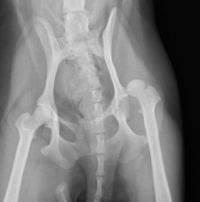

股関節脱臼

必要であれば神経学的検査、関節液検査を行います。診断が難しい場合にはCT画像検査や関節鏡検査、MRI検査を行うこともあります。